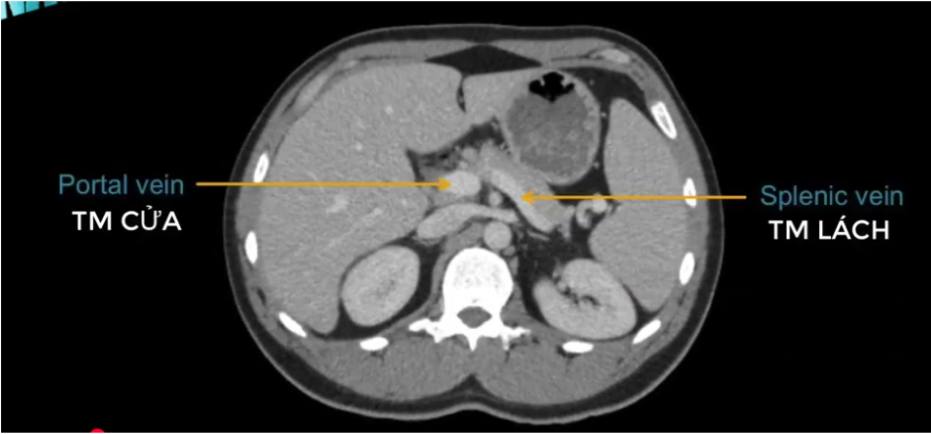

TM gan ở đâu? TM chủ dưới ? ĐM chủ?